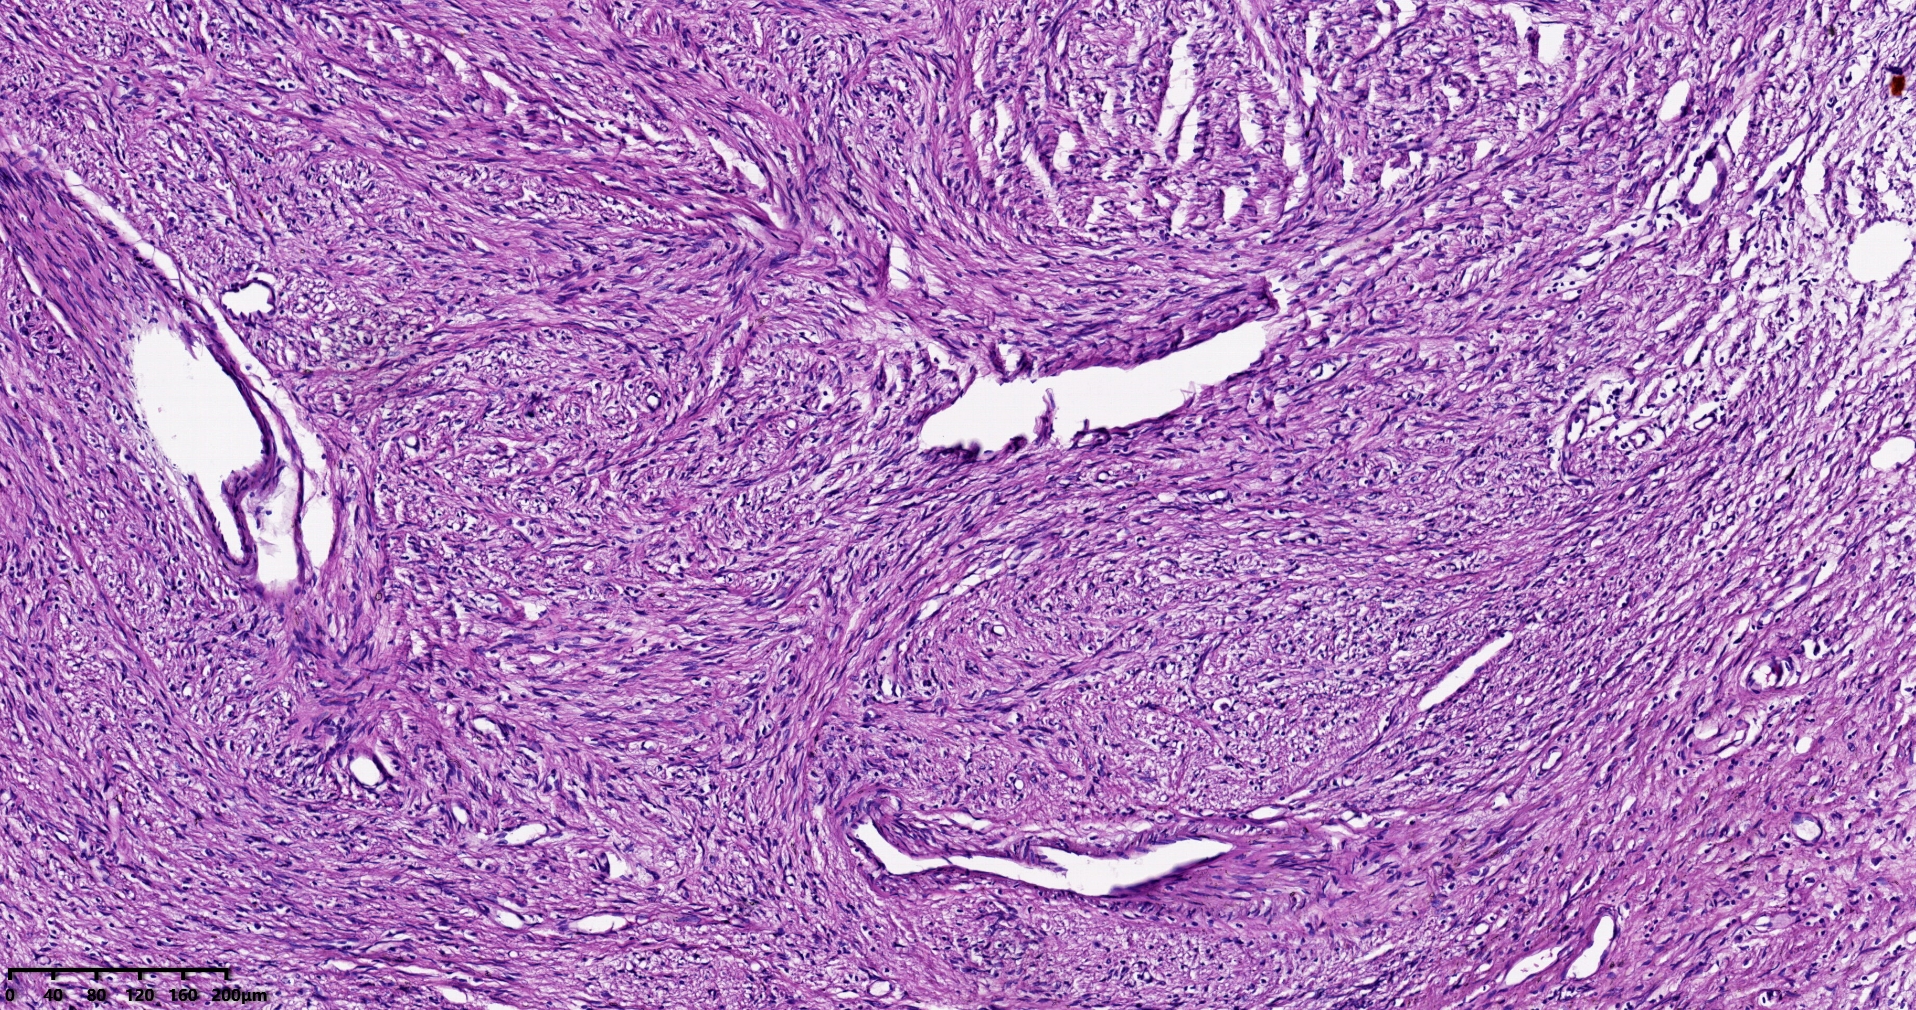

结肠肝曲息肉状肿物,平滑肌瘤?胃肠道间质瘤?炎性纤维性息肉?

大体所见

灰红色椭圆形息肉一个,直径2.5cm,蒂长0.5cm,切面灰白灰红色,质中。

考虑间质瘤?

就HE形态而言,间质瘤的可能性要大一些,建议做免疫组化协助鉴别。